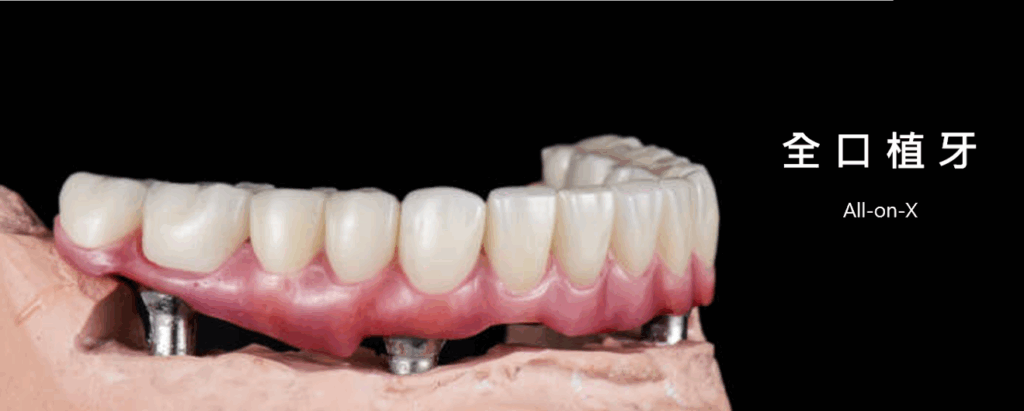

什麼是All-on-X ?

全口植牙是一種先進的牙齒重建技術。它並非一顆顆種植所有牙齒,而是利用精密的規劃,在您的上下顎骨中植入數顆(通常4至6顆)堅固的鈦金屬人工牙根(植體)作為支撐基礎。然後,再將一副製作精良、宛如真牙的「固定式假牙」穩固地安裝在這些植體上。

• All-on-4 / All-on-6: 利用最少數量的植體(上/下顎各4或6顆),以特殊角度植入,常可避開骨質不足區域,減少或避免複雜的補骨手術,縮短治療時間,是高效能的解決方案。

3. 高效重建: 結合原有的兩顆植體與新植入的四顆植體,共計六顆植體作為支撐基礎。利用特殊的連接裝置(如桿柱或橋接設計),為林先生鎖上一組穩固的全口固定式假牙(All-on-6 hybrid prosthesis)